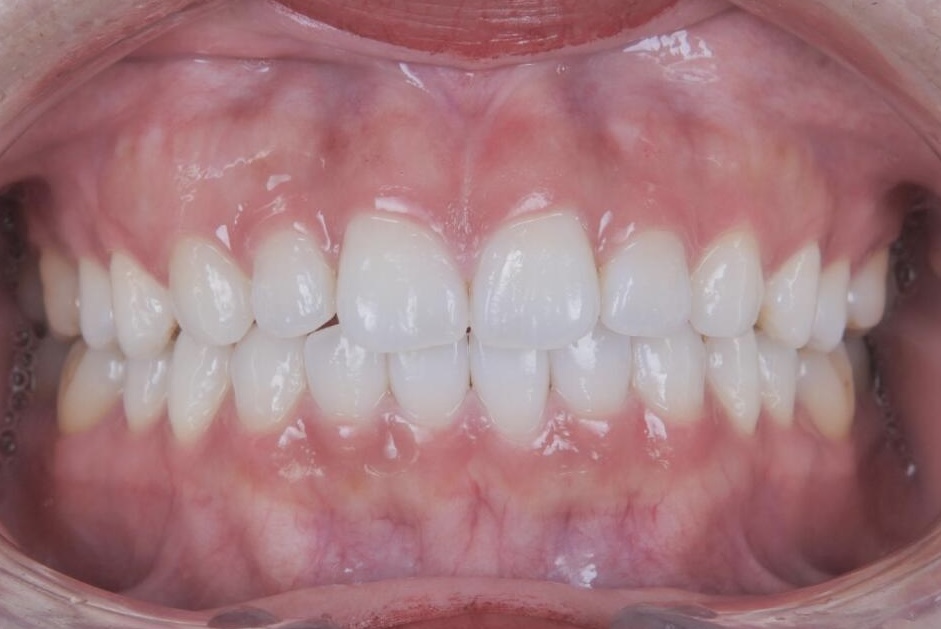

AFTER

治療はマウスピース矯正で行い、治療期間はわずか1年で歯並びが整いました。さらにホワイトニングも併用したことで、歯並びだけでなく歯の色も明るくなり、整った歯並びと白い歯が調和した、より印象的な口元へと改善しています。

治療後は、周囲の方から歯を褒められることが増え、笑顔に自信が持てるようになったとお話しくださり、「本当に矯正してよかった」と、現在もメインテナンスで通院されるたびに嬉しいお言葉をいただいています。また、お子さまのうちお二人も、同じマウスピース矯正で現在当院にて治療を進めており、ご家族で通っていただいている症例です。